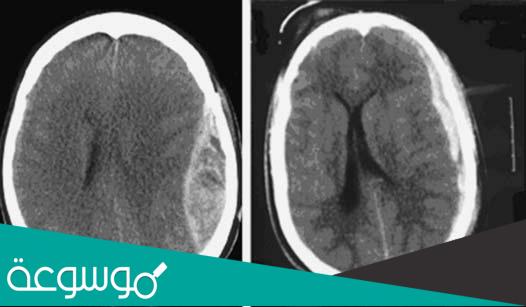

يعتمد العلاج على التشخيص الأولي ، والذي يتم عن طريق تصوير الدماغ ، ثم يتم تطبيق الخيار الأنسب لعلاج المريض ، عن طريق الأشعة المقطعية للدماغ ، والرنين المغناطيسي ، وتخطيط كهربية الدماغ ، وعلى أساس يتم تحديد ما إذا كان المريض في حجة للتدخل الجراحي ، والذي يتم عن طريق إزالة الجلطات الدموية في الدماغ ، وذلك بسبب طبيعة المكان المصاب وإمكانية إزالة الورم، هناك بعض الحالات التي يتطلب فيها التدخل الدوائي ، من خلال بعض الأدوية الكيميائية القادرة على إزالة شدة الورم ، وقد يكون هذا الاعتماد على الدواء قبل وبعد التدخل الجراحي.